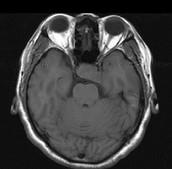

问题 男,41岁,头昏伴头痛1年,请根据所提供图像,选择最可能的诊断()

选项 A.(鞍区)脑膜瘤 B.(鞍区)颅咽管瘤 C.(鞍区)生殖细胞瘤 D.(鞍区)转移瘤 E.(鞍区)垂体腺瘤

答案 E